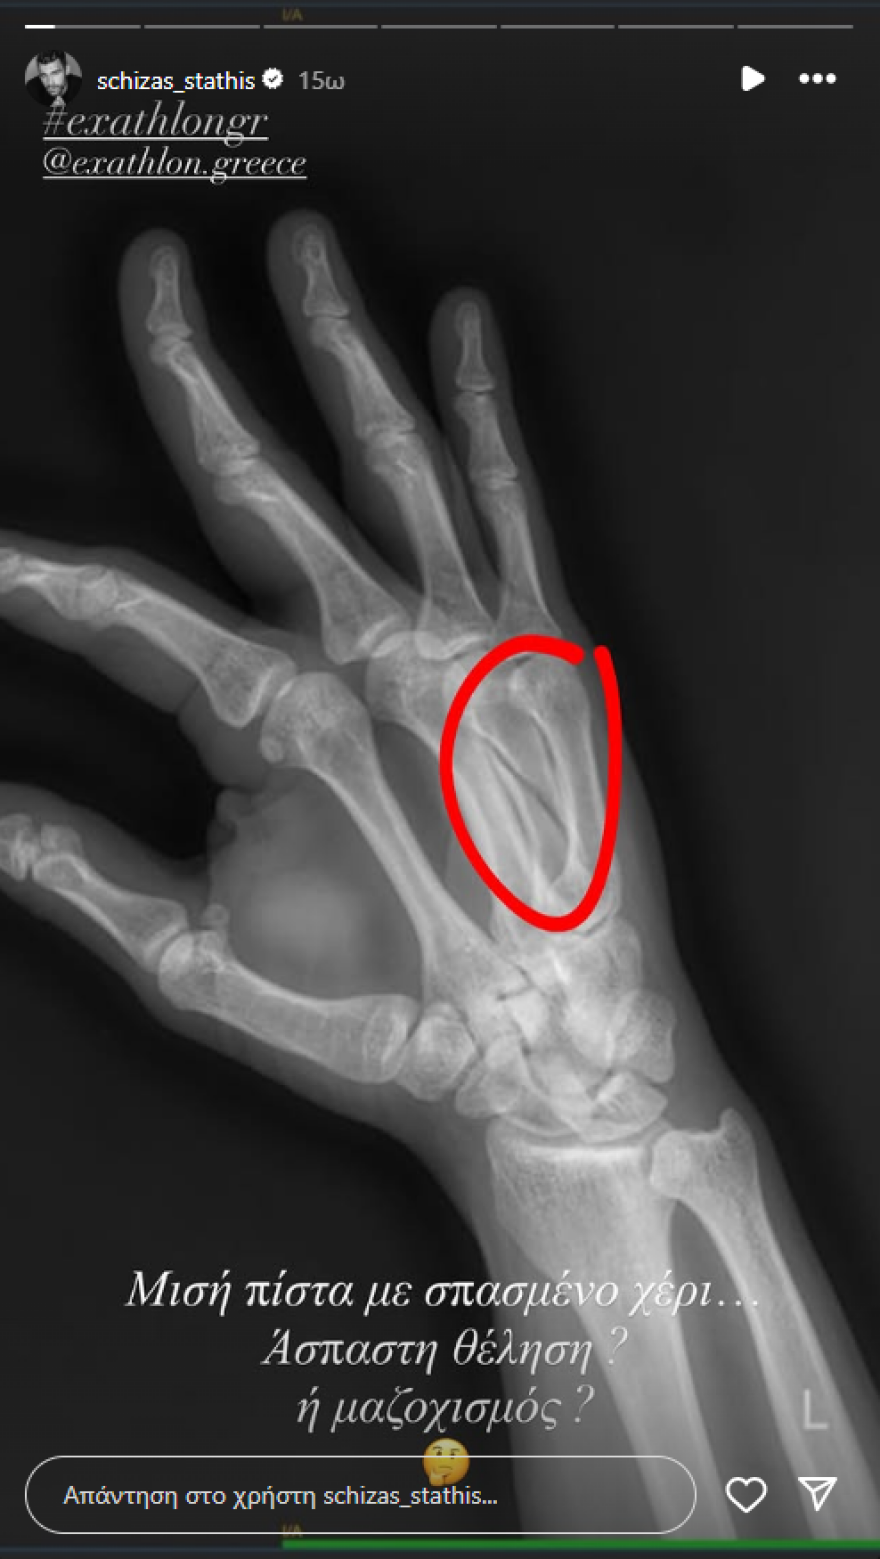

«Μισή πίστα με σπασμένο χέρι - Άσπαστη θέληση ή μαζοχισμός;»

Λίγες ώρες αργότερα, ο Στάθης Σχίζας ανέβασε το πρώτο του story στον προσωπικό του λογαριασμό στο Instagram. Σε αυτό φαίνεται μια ακτινογραφία του χεριού του. Πάνω σε αυτή, έγραψε: «Μισή πίστα με σπασμένο χέρι. Άσπαστη θέληση ή μαζοχισμός;». Στάθης Σχίζας: Η πρώτη ανάρτηση μετά την αποχώρησή του από το Exathlon και τον τραυματισμό του